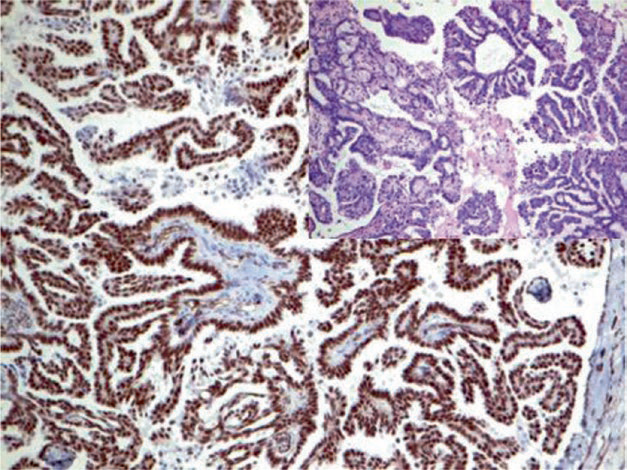

Figure 1. Ovarian serous carcinoma, immunohistochemistry shows strong nuclear positivity for WT-1.

Figure 2. Ovarian serous carcinoma, immunohistochemistry shows cell membrane staining for CA125.